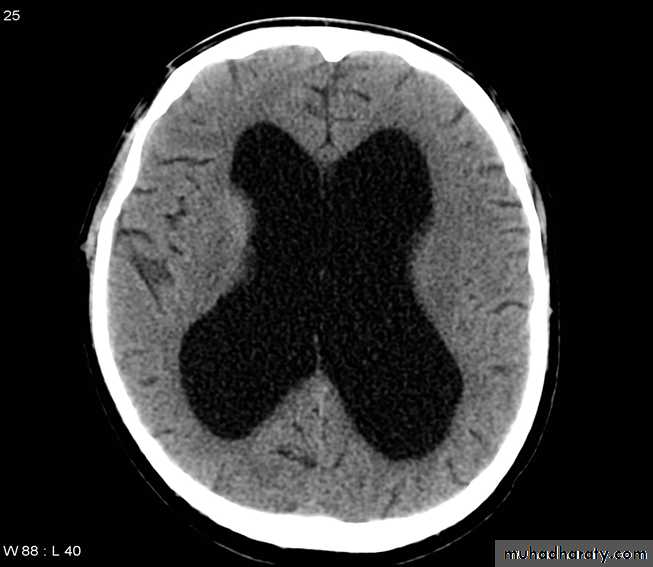

Hydrocephalous

2 types

Obstructive ( non – communicating )

Non –obstructive ( communicating )

No obstruction of the ventricular pathway , but the absorption of the csf at the level of arachnoids' granulation is occluded secondary to lodge by blood clot or inflammatory cell or infection post meningitis most commonly to occur post SAH .

90 % present with obstructive hydrocephalous at the level of the 4Th V. with dilatation of the lateral V. ( body , frontal , temporal & third ventricle )